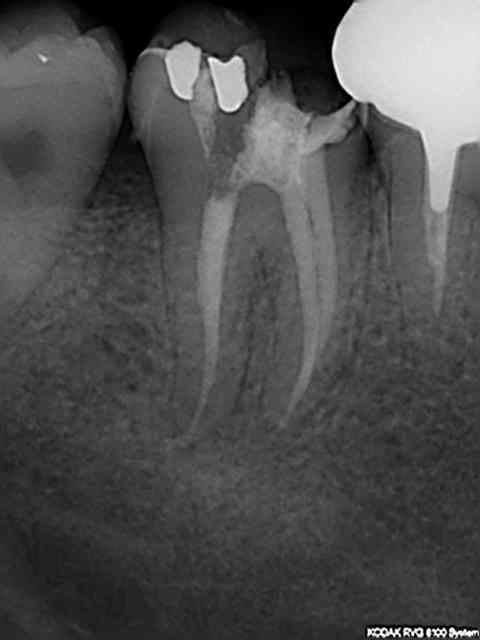

Tiens les endos de la semaine, que d'apex défoncés !-))

La 47 en fin le distal est obturé au système B (bouchon apical) et au mac spaden pour la partie coronaire, tu vois la différence à la radio ? Alors l'apex défoncé il faut avoir l'oeil ! peut etre mais à 25 centièmes et à conicité 6 %........-))